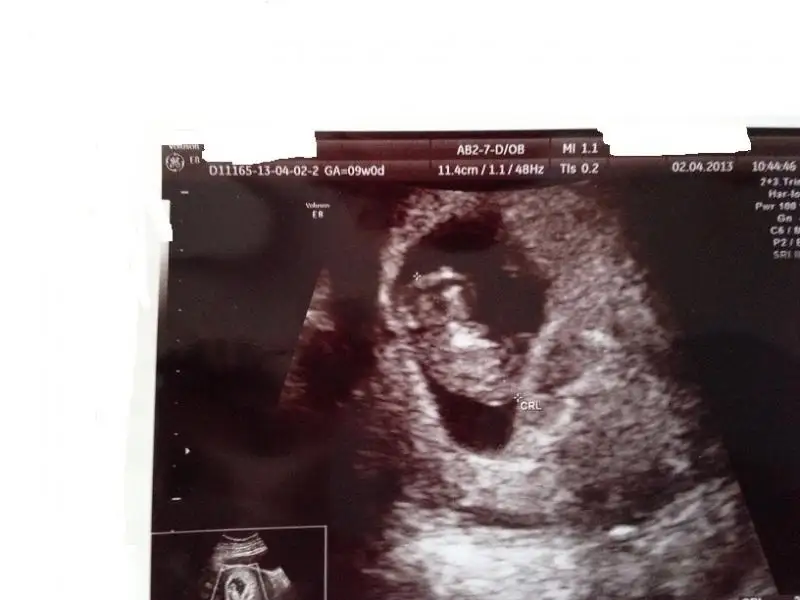

dr soylemeden siz gorun genital nub teorisi ( bebegin cinsiyeti)

oğlum diyemeyeceğim ya o içimi yakıyor.kayınvalidem haklıymış annemin oğlu yok senin de olmaz demişti.eşime yalvardım kıbrısa gidelim diye be ALLAH karşı gelemem 10 tane kızımda olsa gitmem dedi.doktorumda çok üzüldü beni çok seviyor kadının gözleri doldu üzülme yanılabiliyorumda arasıra diyor ama kıza hazırlan dedi 13.haftadayım od anuba göre bakıyormuş

canım 12 + 1di ordaki ertesi gün başka hastaneye gittim 11+4 yazmış ultrason kağıdına 4 5 günlük geri normal adetime göre doktorun yazdığı halbuki ilk gittigim gününla aynı bebek demişti

9 haftalik sevincim bugun son buluyor

Kurtaj olucam o kadarda cok istemistikki nasip